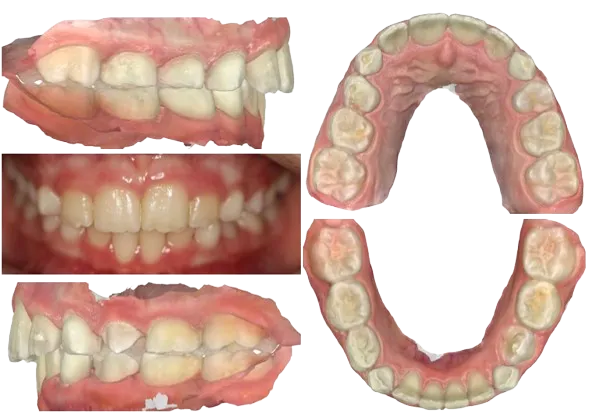

With the revised staging, her teeth demonstrated improved tracking and February 2024 we completed her Phase I with delivery of an upper and lower Vivera retainer to be worn at home and at night. Retainers will be replaced as primary teeth exfoliate and retainer is unable to stay in place.

Treatment Review

Patient, her parents, and I were pleased with the outcome. We accomplished the objectives of improved overjet, decreased overbite, aligned teeth, and broader arches. I was very impressed with patient and her excellence with Invisalign.

Critically reviewing my final records, I wish I had detailed #9 to have additional mesial root tip. Also #23 would have benefited from mesial out rotation, and more labial root torque (left buccal shot comparing the facial of #23 to 24).